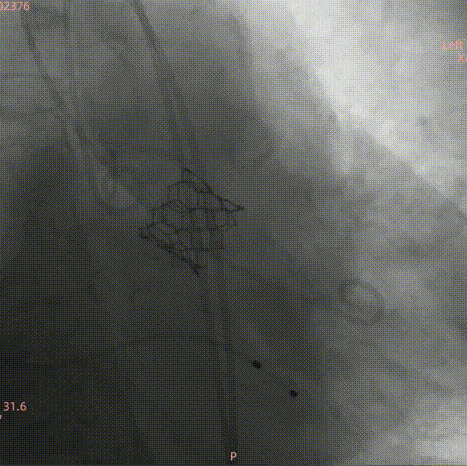

主动脉瓣呈三叶瓣,收缩期瓣环:299.8mm²;收缩期流出道:290.9mm²;

法式窦空间小;STJ高度17.4mm,均径26.4mm;升主动脉40mm处均径36.1mm;心脏角度52°;

LCA:10.4mm;RCA:13.2mm;窦部空间小,右冠风险不排除;

瓣叶增厚,轻度钙化,分布在瓣缘和窦底;

对合缘对齐(Commisure Alignment)角度为 83°;室间隔膜部长3.6mm;

使用20mm瓣膜进行术前模拟并评估冠脉遮挡风险;

外周入路血管条件,主动脉弓、降主动脉及腹主动脉部分部位存在钙化。